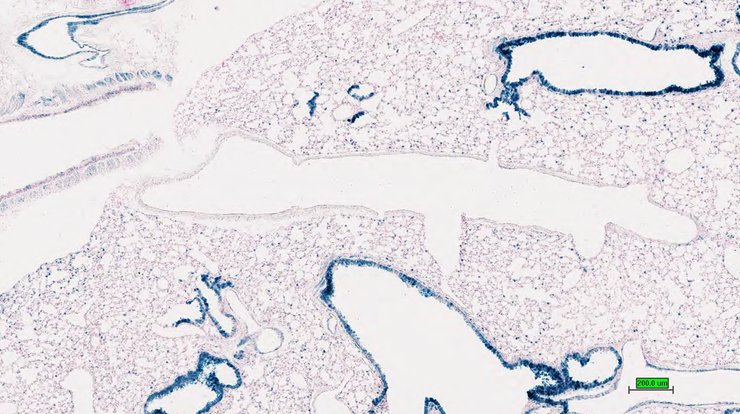

TS28: lung Present UC Davis_1883368

Specimen UC Davis_1883369: postnatal adult; Fzd5tm1.1(KOMP)Vlcg/Fzd5+ (more )

Structure Level Pattern Image Note

TS28: lung Present UC Davis_1883369

Specimen UC Davis_1883370: postnatal adult; Fzd5tm1.1(KOMP)Vlcg/Fzd5+ (more )

TS28: lung Present UC Davis_1883370

Specimen UC Davis_1883371: postnatal adult; Fzd5tm1.1(KOMP)Vlcg/Fzd5+ (more )

TS28: lung Present UC Davis_1883371